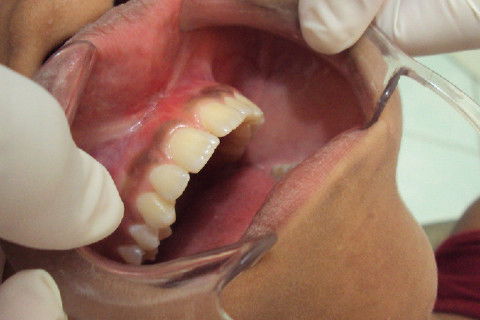

Lateral

Paciente JC, sexo feminino, 13 anos, com uma boa higiene oral, apresentava freio labial superior com insersão muito baixa, ocasionando em diastemas dos incisivos centrais superiores.